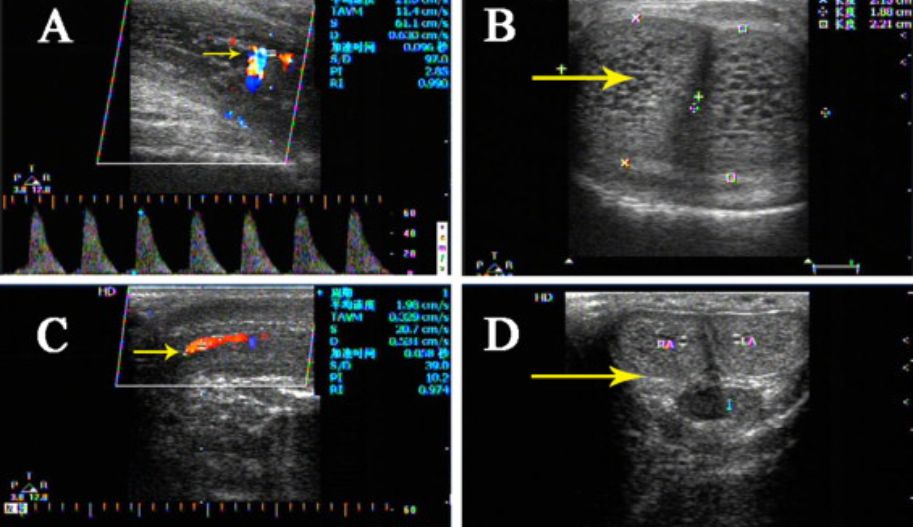

Renal doppler çekiminde ekrana mavi ve kırmızı renklerden oluşan görüntüler yansır. Bu renkler damarlarda bulunan kanın hız ve akış yönünü belirtir.

Renal arter stenozu tanısı için Doppler ultrason kriterleri, stenoz seviyesinde elde edilen direkt bulgulara (proksimal kriterler) veya darlık bölgesinin distalinde renal vaskülaritede gözlenen akım değişikliklerine (distal kriterler) göre iki gruba ayrılabilir.

Doppler US ile daha erişilebilir arteriyel segmentlerdeki stenozun distalinde (yani hiler veya interlobar arterler) bakılan kriterler. Bunun mantığı, hemodinamik olarak anlamlı bir stenozun distalindeki renal hilustaki akışın sönümlenmesi ve tepe sistolde yavaş bir artış göstermesi gerektiğidir. Bu fenomene “tardus-parvus” etkisi denir. Tardus yavaş ve geç, parvus ise küçük anlamına gelir. Tardus, dalga formunun sistolik ivmesinin yavaş olması ve bunun sonucunda sistolik zirveye ulaşmak için zamanın artması gerçeğine atıfta bulunur. Parvus, sistolik tepe noktasının düşük yükseklikte olması gerçeğine atıfta bulunur, bu da yavaş bir hıza işaret eder. Ancak bu bulgunun varlığı tanı koymada yardımcı olsa da yokluğu renal arter stenozunu dışlamaz. Aterosklerozlu hastalarda damar esnekliği azalabilir, bu da parvus-tardus dalga formu morfolojisini daha az belirgin hale getirir.

Doppler ultrason nakil böbreklerin değerlendirilmesi için en çok tercih edilen görüntüleme yöntemidir. Nakil böbrek sağ veya sol iliak fossada bulunur. Greftin yüzeysel yerleşimi US incelemesini doğru ve ideal kılmaktadır. Renal greft, hemen veya daha sonra meydana gelebilecek çeşitli patolojik değişikliklere karşı hassastır.

Dopplerde renal arter RI artışının, akut rejeksiyon ve ATN varlığı ile ilişkili olduğu bildirilmiştir. Öte yandan böbrek nakli yapılan hastalarda yüksek serum kreatinin düzeyleri yüksek RI değerleri ortaya koymaktadır. Bu nedenle renal arter RI değeri , greft fonksiyonunun iyi bir göstergesidir.